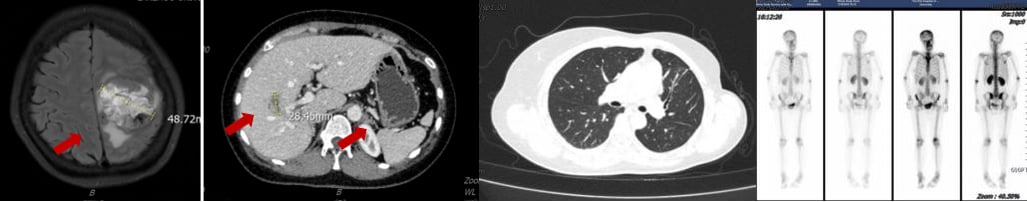

在无进展生存(PFS)长达6年8个月后,2022年2月,患者再次出现胸闷、气短、乏力等症状。影像学检查显示,疾病进展为肝、骨、肺、胸膜、脑多发转移,并伴有左侧胸腔积液。肝穿刺活检病理证实为转移性低分化腺癌,免疫组化提示ER高表达,HER2(2+),FISH检测显示HER2扩增,再次明确为HER2阳性乳腺癌。

此时,曲妥珠单抗(一种经典的HER2靶向药)已纳入医保,为患者带来了新的希望。MDT讨论后,患者接受了以下解救治疗:

- 靶向联合化疗:TCbH方案(曲妥珠单抗+白蛋白结合型紫杉醇+卡铂)4周期,随后TH方案(曲妥珠单抗+白蛋白结合型紫杉醇)2周期。

- 骨转移治疗:定期静脉注射唑来膦酸,并口服碳酸钙D3片和骨化三醇进行补钙。

令人惊喜的是,治疗后患者疗效评价为部分缓解(PR),特别是颅内病灶达到了完全缓解(CR),且长期无症状。这充分证明了HER2靶向治疗的强大效果,即使是脑转移这种棘手的情况,全身治疗也能取得显著成效。随后,患者进入维持治疗阶段,使用氟维司群+曲妥珠单抗+戈舍瑞林,病情持续稳定。